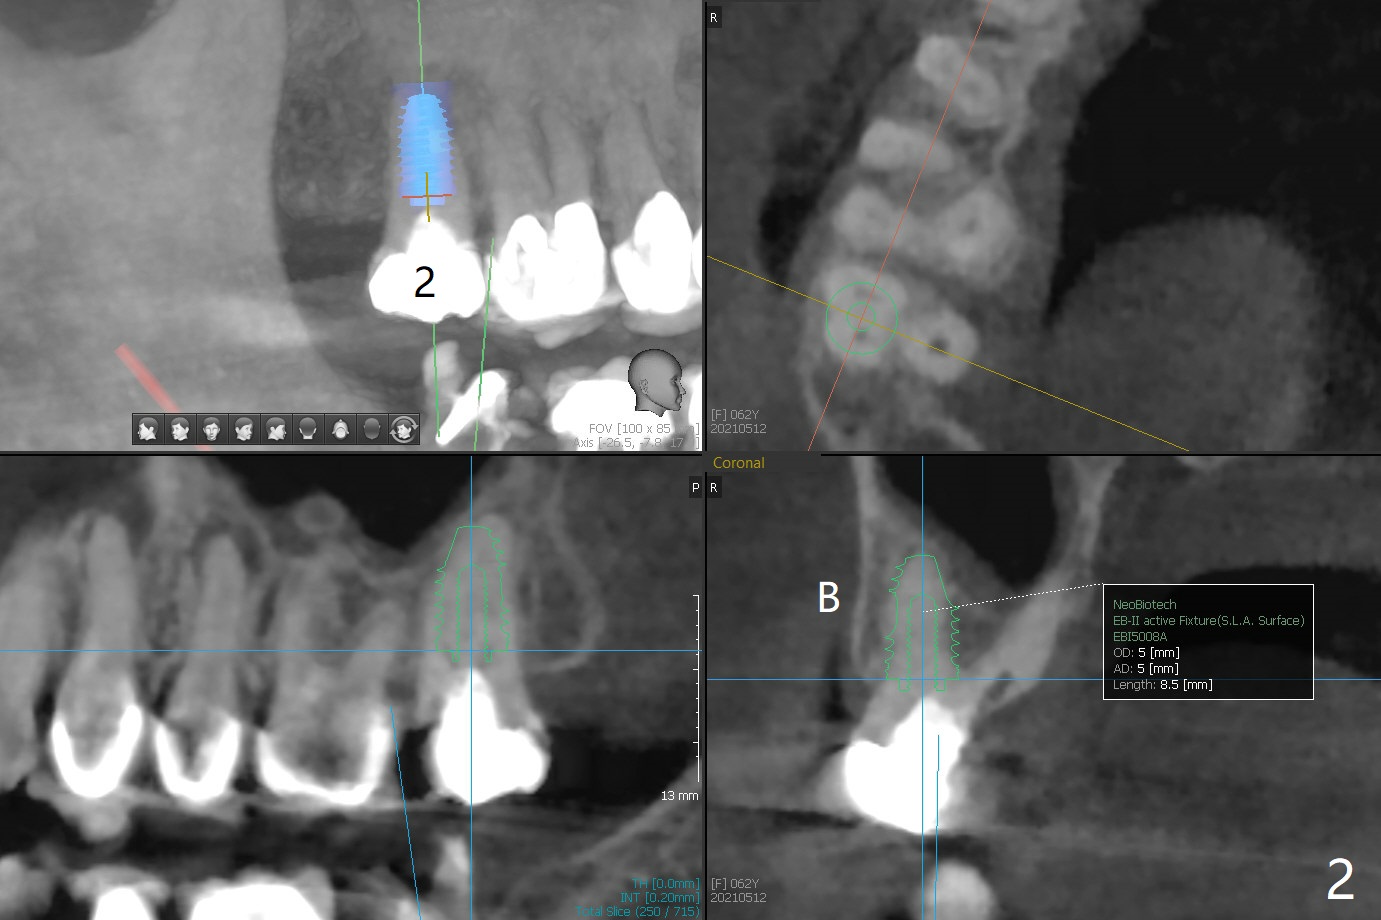

Immediate Upper and Lower 2nd Molars

A 62-year-old woman requests implants at #2 and 31. PRFx2

31 Surgery

2

31